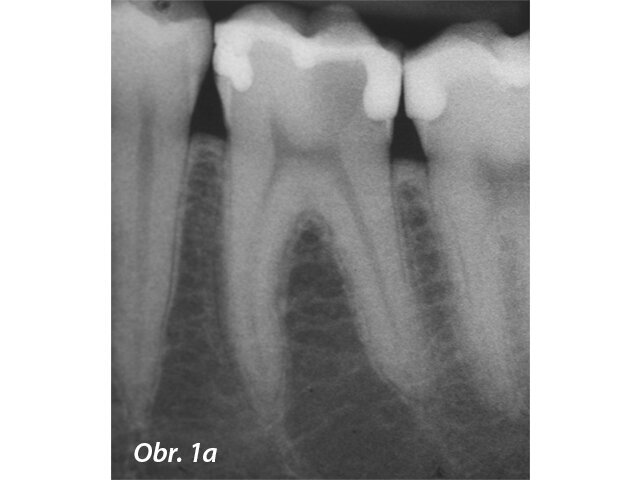

Kořenové perforace

Perforace v dřeňové dutině nebo kořenovém kanálku významně mění prognózu zubu. Oprava perforace pomocí biokompatibilního těsnicího materiálu jako je MTA může ohrožené zuby ušetřit (Mente a spol. 2014) (obr. 3a–e).

Radiolucence v krčkové části špičáku

Původní stav se zaplněnou perforací

Postoperační RTG se zaplněným kanálkem